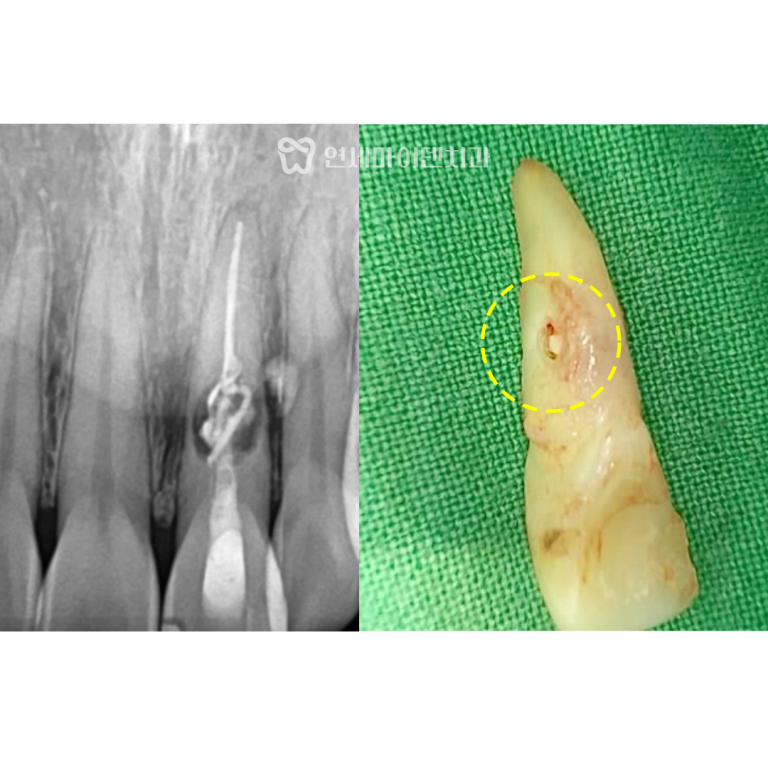

결국 잇몸을 열어 내부 상태를 확인한 결과,

치조골 손실이 심하게 진행돼 있었고,

더는 회복이 어려운 상태라고 판단해

이 치아는 발치 후 즉시 임플란트 진단을 내렸습니다.

발치 당시엔 염증 부위를 철저히 분리하여,

건강한 뼈를 기반으로 고정력을 확보한 뒤

뼈이식과 차폐막을 함께 적용했습니다.